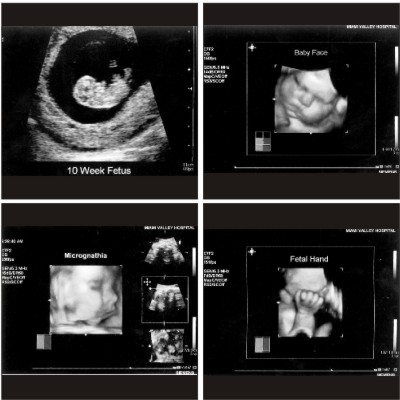

The Sonoline Antares ultrasound system provides best-in-class Doppler, 2D and 3D imaging, and for real-time premium performance 4D studies, new fourSight 4D imaging ultrasound technology.

4D imaging helps physicians and sonographers to clarify exactly what they are seeing in 2D imaging. In addition, it helps to demonstrate the stages of fetal development and may contribute to parental bonding with their unborn child. fourSight 4D can show the fetal anomalies much better detail which can be used for the correction of the anomaly also. Using the technology physicians will be able to see more fetal activity, or certain aspects that ever obtained.

It has a wider range of applications in the field of antenatal and postnatal management, diagnosis of uterus and breast as well as it could be used during 4d needle-guided biopsy.